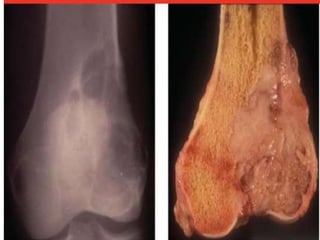

Conventional/classic variant

• Most prevalent,80% of osteosarcomas,

metaphyseal origin

• High grade

• Mixed osteolytic/ blastic lesion.

• Based on predominant EC matrix ,(osteoblastic,

chondroblastic, fibroblastic)